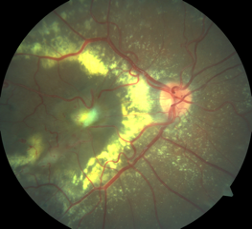

Paciente masculino, 8 anos, apresenta redução da acuidade visual somente no olho direito, há cerca de 2 meses.

Trata-se da doença de Coats, caracterizada por telangiectasias, microaneurismas e exsudação. É mais comum em homens com menos de 10 anos de idade e frequentemente é unilateral.

tto da doença de Coats

A fotocoagulação deve ser feita nas áreas de não perfusão para reduzir o risco de neovascularização e favorecer a reabsorção dos exsudatos.